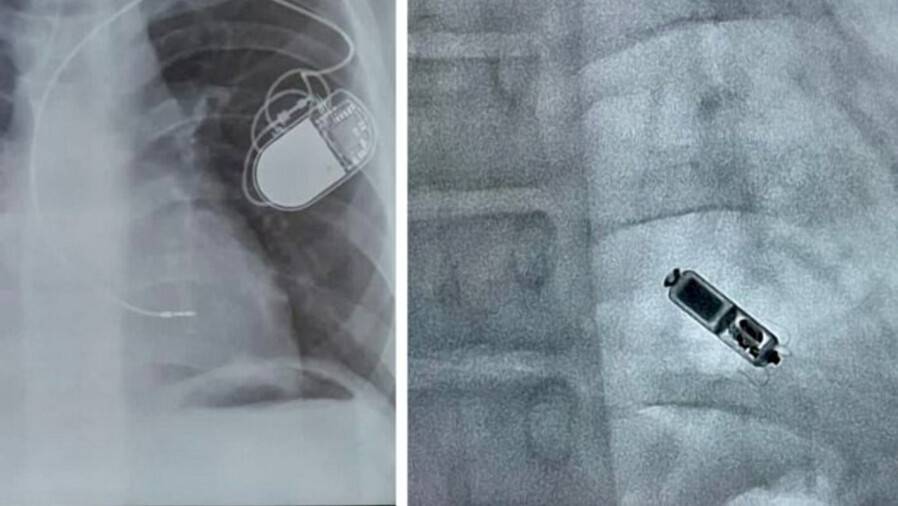

В Нур-Султане в Национальном научном кардиохирургическом центре врачи успешно провели имплантацию самого маленького в мире электрокардиостимулятора Micra AV подростку, сообщает "Sputnik Казахстан".

У 14-летнего мальчика врождённый порок сердца. В семилетнем возрасте ему исправили дефекты межжелудочковой перегородки и трикуспидального клапана, но после возникли осложнения. После операции ему имплантировали привычный всем кардиостимулятор с электродами. Но со временем он перестал подходить пациенту по размерам, электрод начинал натягиваться.

"Мы решили удалить прежнюю систему ЭКС, так как она уже не подходит пациенту. После чего мы провели имплантацию нового безэлектродного ЭКС Micra AV. Состояние пациента заметно улучшилось, а синхронизация между предсердиями и желудочками достигла 80%", – рассказал заведующий отделением интервенционной аритмологии центра Аян Абдрахманов.

Micra AV – это самый маленький безэлектродный электростимулятор в мире. Он имеет размер таблетки. Его устанавливают только в правом желудочке – одной камере сердца, но аппарат работает как двухкамерный за счёт распознавания предсердных сокращений.